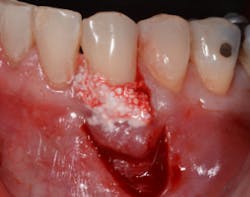

The Bernotti V-Y Flap involves making a submarginal supraperiosteal V-shaped incision 1 mm to 2 mm apical to the mucogingival junction, creating a pedicle flap (figures 2 and 2a). This flap is extended one tooth mesially and distally to the recession defect. It is important to note that the flap should leave the adjacent papillae intact in order to preserve blood supply. An intrasulcular incision is then made with a microsurgical blade to allow for coronal movement of the marginal tissue without tension (figure 3). The root is then scaled/root planed and chemically modified with an amoxicillin slurry for three minutes (figure 3a).